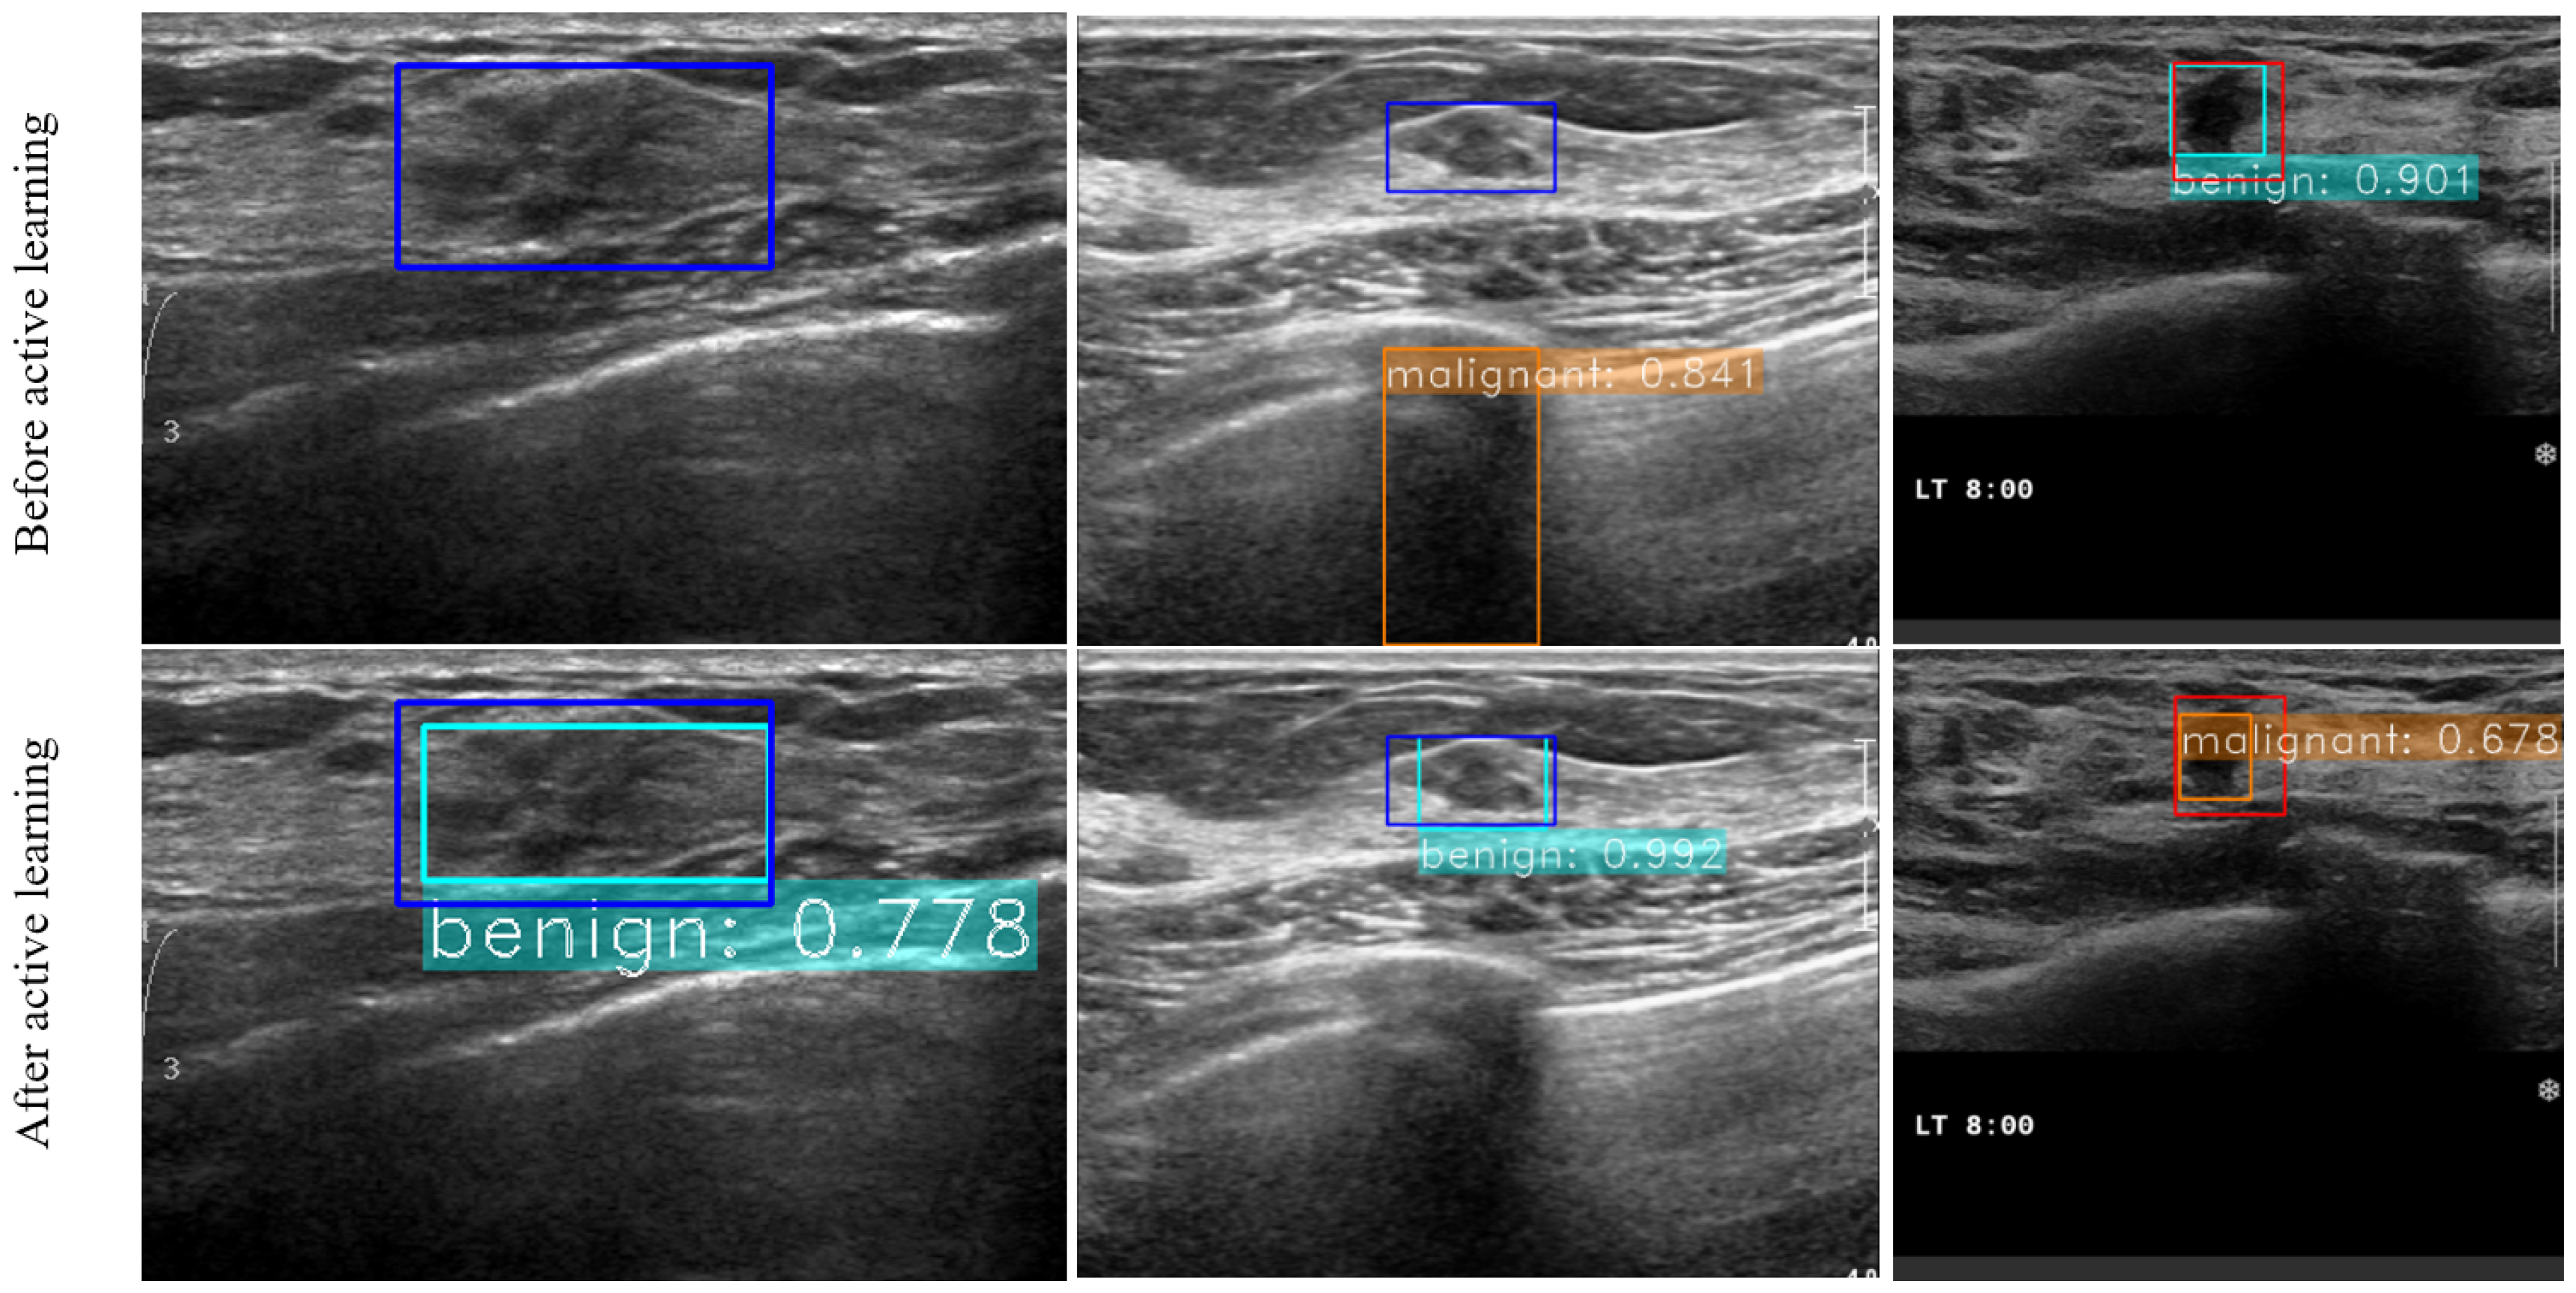

3.3. Experiments for Active Learning on SNUBH Dataset

3.4. Experiments on Comparable Object Detectors